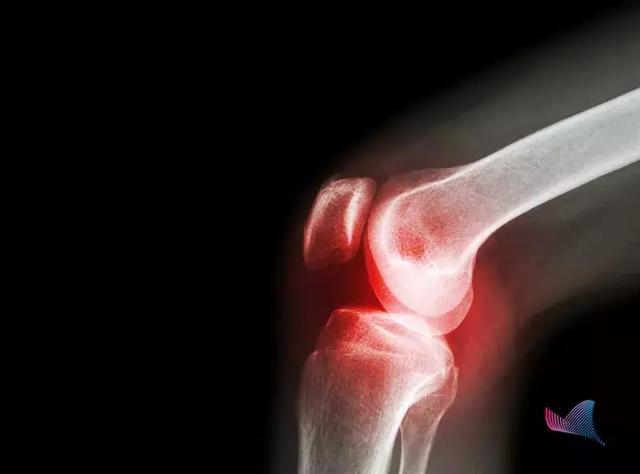

提到类风湿关节炎,很多人的想法都存在着误区:这是一种老年疾病、和年轻时候腿部着凉有关……事实上,这是一种自身免疫性疾病。

患者体内炎症因子水平升高,累及到关节,形成滑膜炎症、骨关节对称性的破坏等,最终可导致关节畸形和功能丧失。而这一疾病的根本病因尚未明确,可能与基因、感染、性激素等多种原因有关。对于患者来说,类风湿关节炎带来的疼痛是一种长期性、慢性折磨,影响着他们的日常生活和美好心情,让他们的世界暗淡无光。